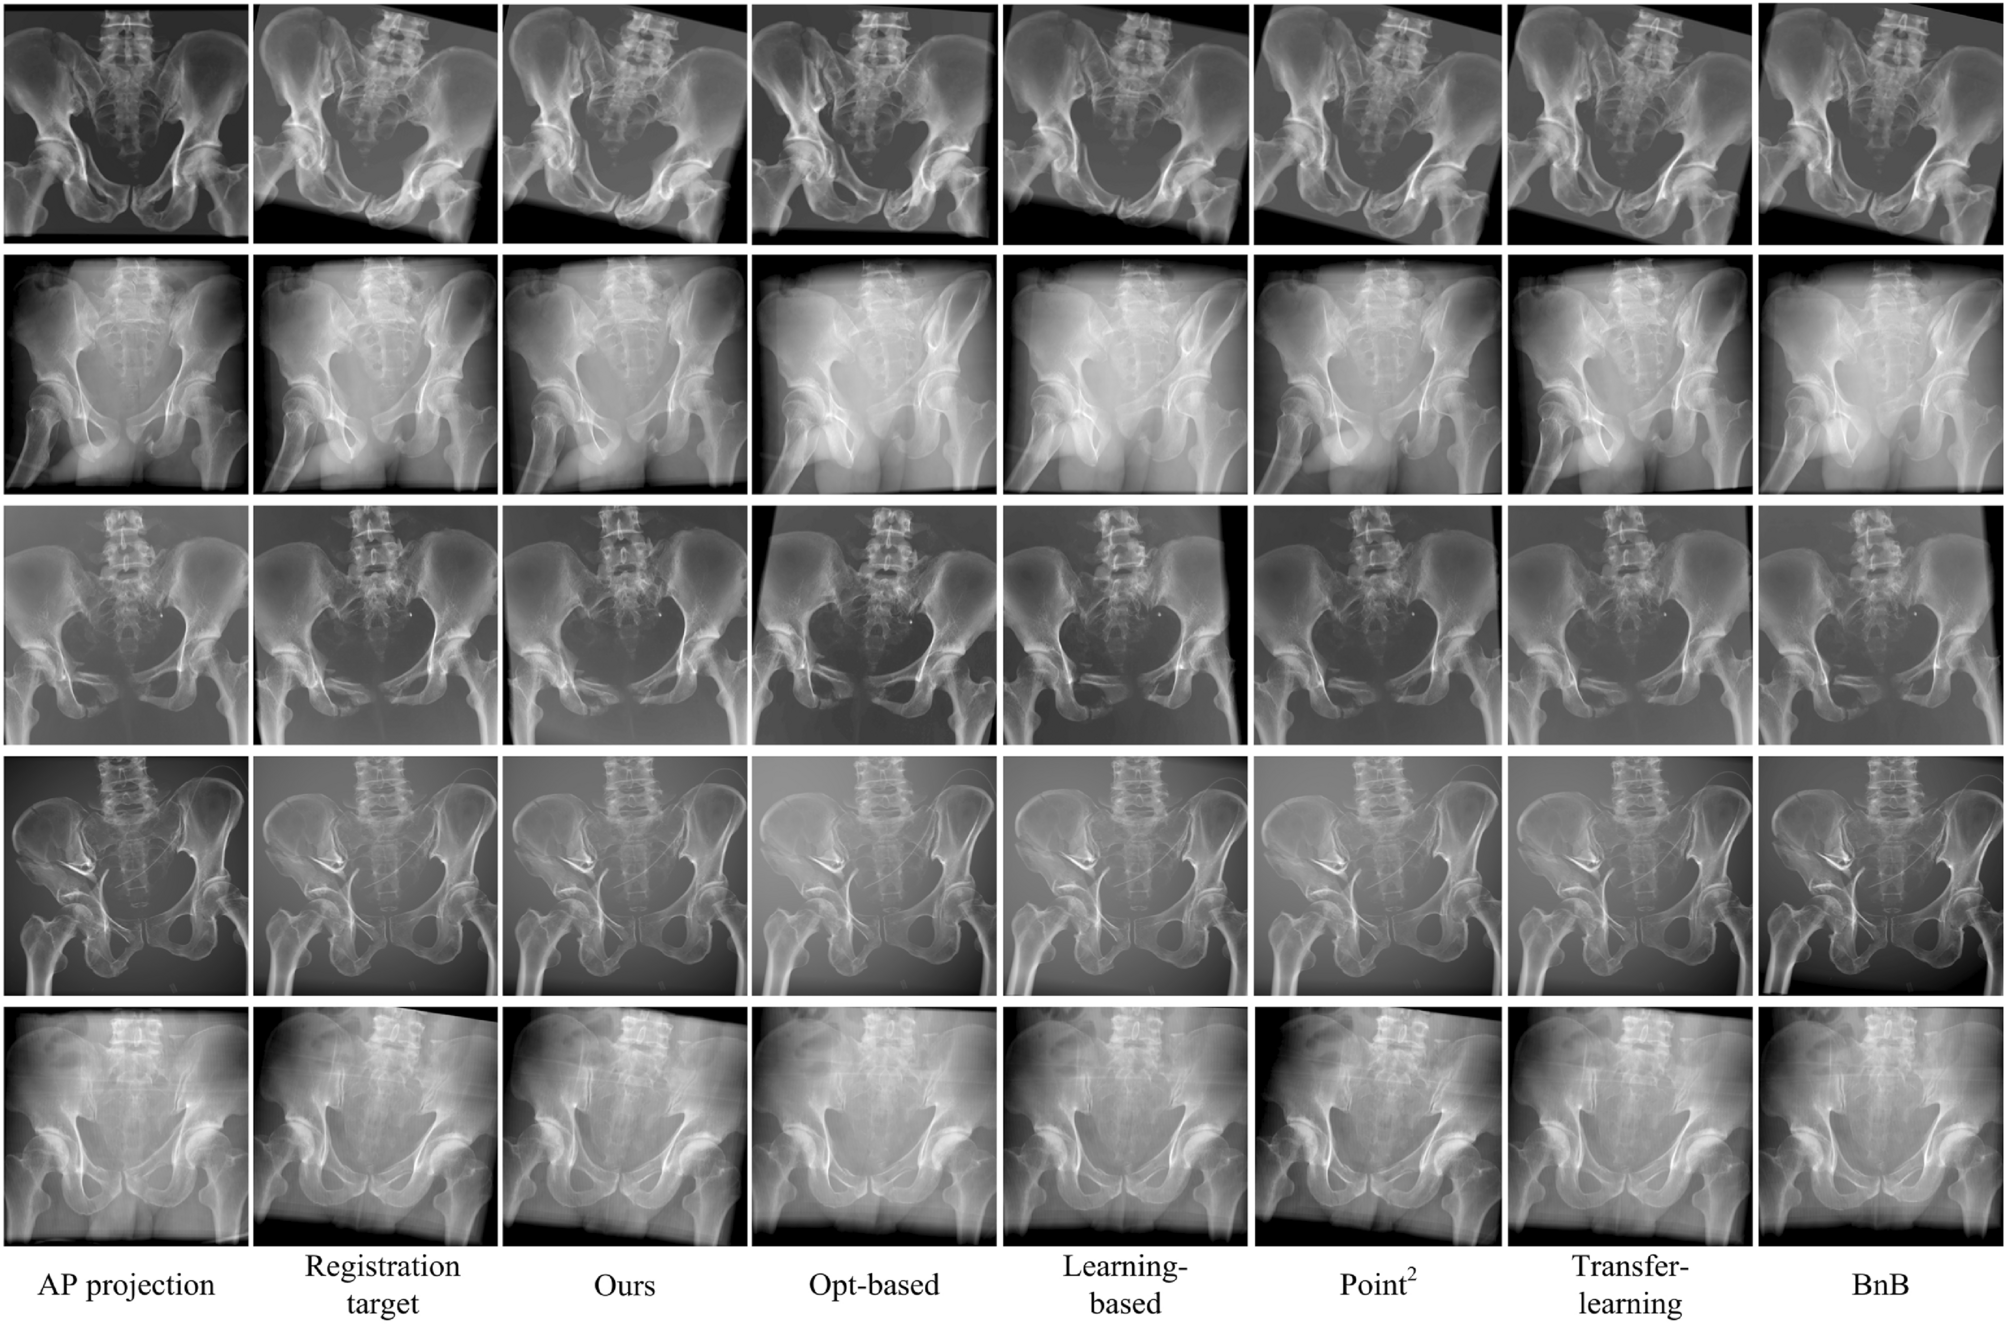

Visualization of synthetic DRRs registration comparison.